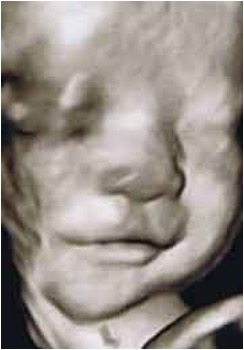

35週。微笑しています。

※画像はすべて4Dエコーによるものです。